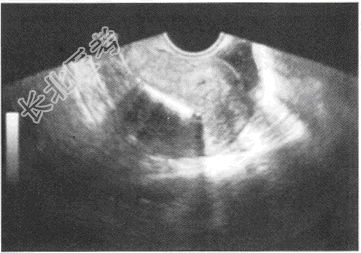

- 单项选择题患者,女性, 40岁,妇科超声检查如图, 强回声所示为

A、子宫钙化环

B、孕囊

C、子宫肌瘤

D、宫内节育器

E、子宫肌瘤钙化